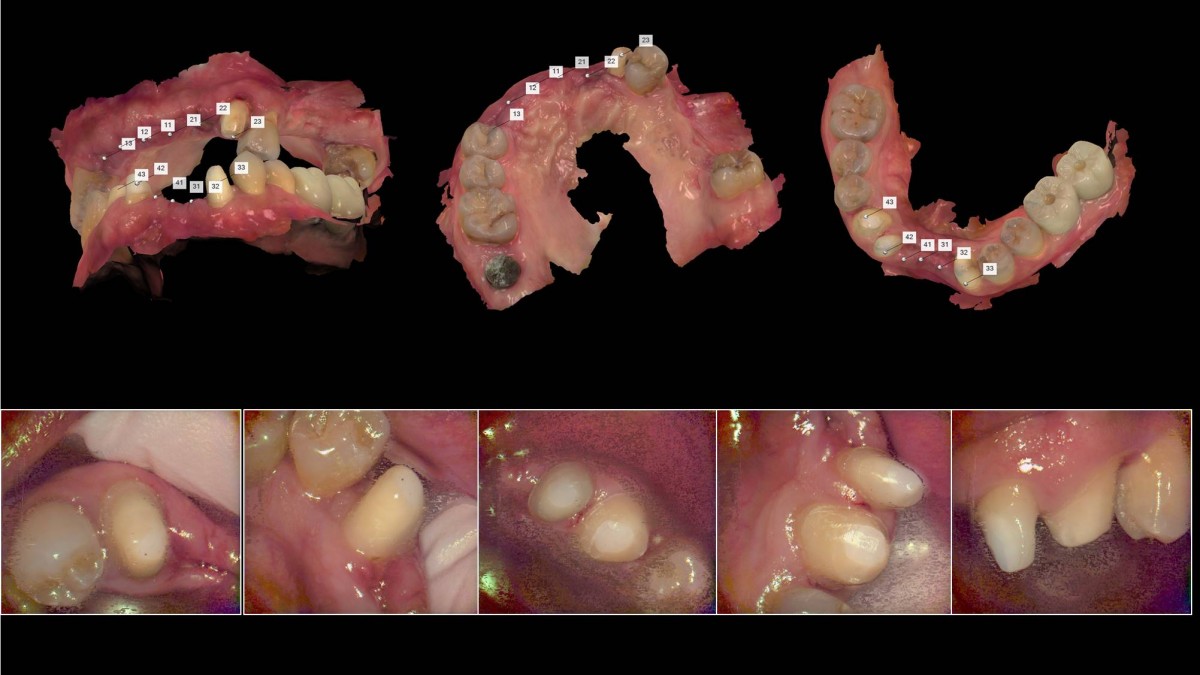

<GCpbc> A 58-year-old male is a patient undergoing implant installation in various parts. The old Br of the anterior maxilla has fallen

off and it is no longer possible to maintain it even temporarily, so a

treatment plan for the anterior teeth was made.